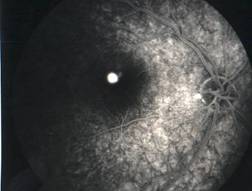

RETINITIS PIGMENTOSA |

|

Retinitis pigmentosa is the most common of a group of hereditary progressive retinal degenerations or dystrophies. There is considerable variation and overlap among the various forms of retinitis pigmentosa. Common to all of them is progressive degeneration of the retina, specifically of the light receptors, known as the rods and cones. The rods of the retina are involved earlier in the course of the disease, and cone deterioration occurs later. In this progressive degeneration of the retina, the peripheral vision slowly constricts and central vision is usually retained until late in the disease. Etiology

Ophthalmic features

Diagnosis